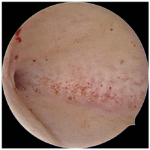

● Infertility Evaluation: To check for blockages, scar tissue, or uterine shapes (like a septum) that might prevent pregnancy.

● Abnormal Uterine Bleeding: To investigate heavy periods, bleeding between periods, or post-menopausal bleeding.

● Polyps and Fibroids: To detect and remove non-cancerous growths inside the uterus.

● Recurrent Miscarriage: To identify if uterine abnormalities are causing pregnancy loss.

● Adhesions (Asherman’s Syndrome): To remove scar tissue inside the uterus that can cause absent periods and infertility.